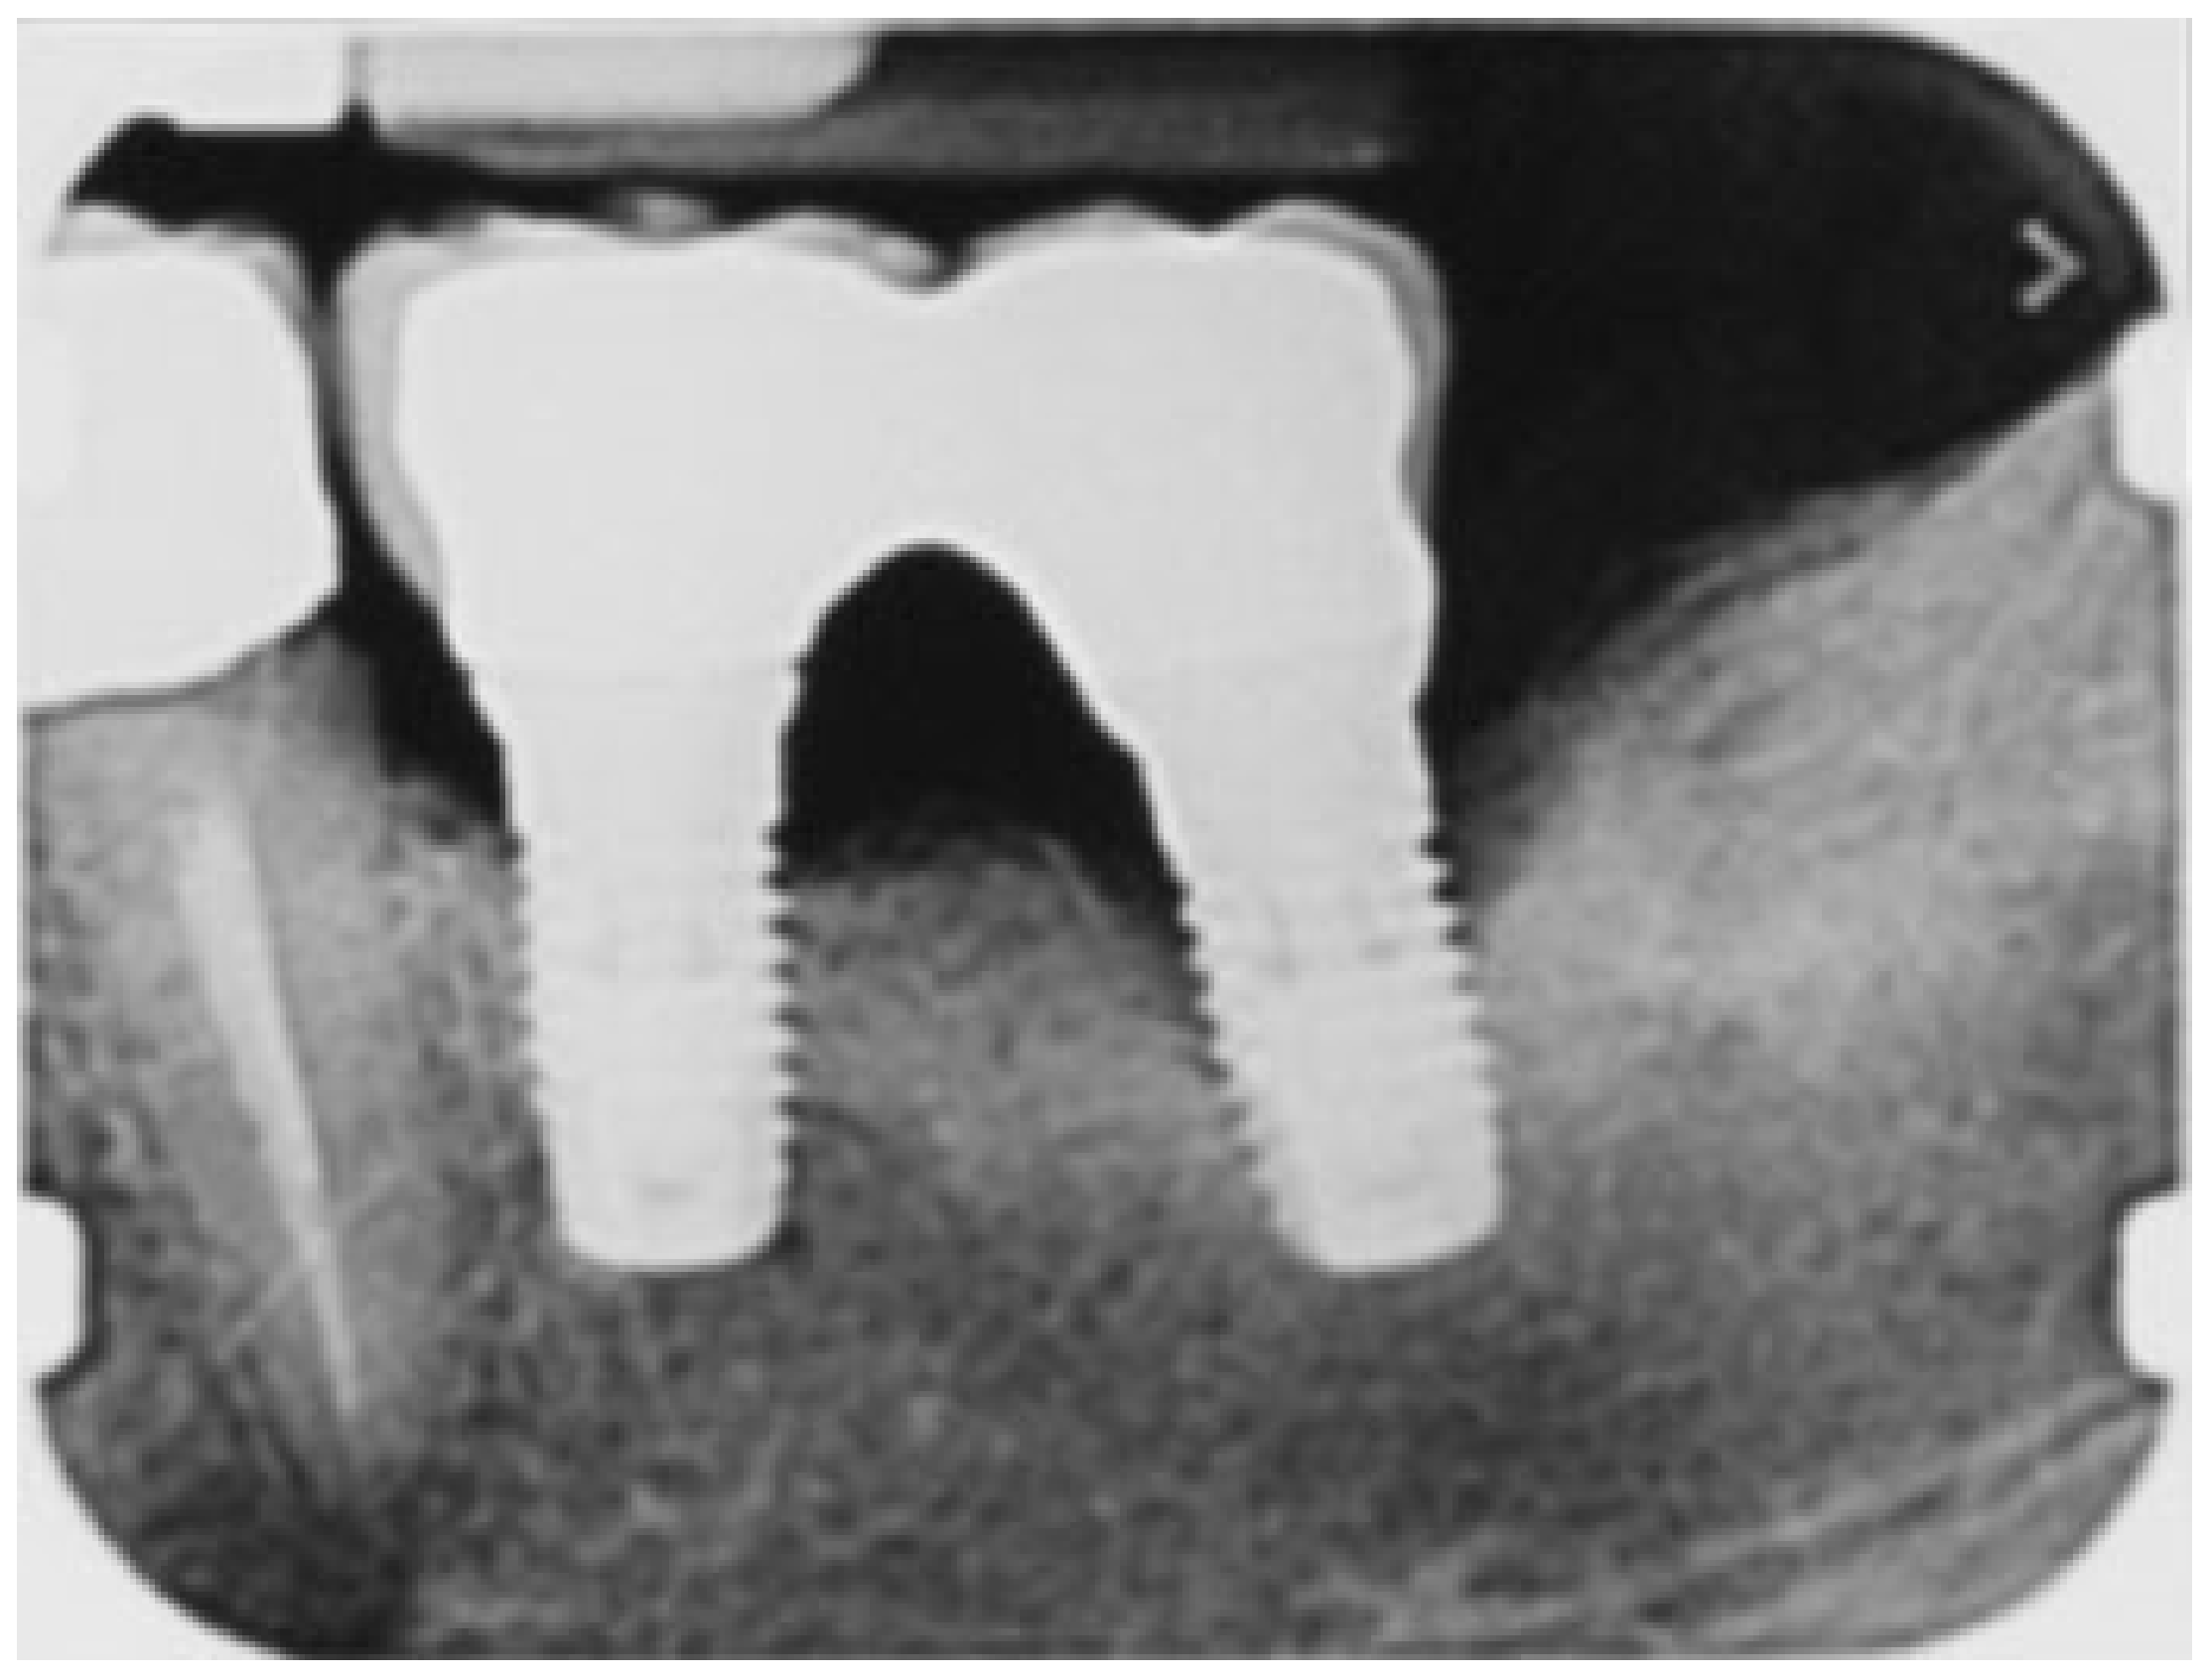

Figure 2.

Rx periapical before peri-implant therapy: infra-bony defect around the distal implant.